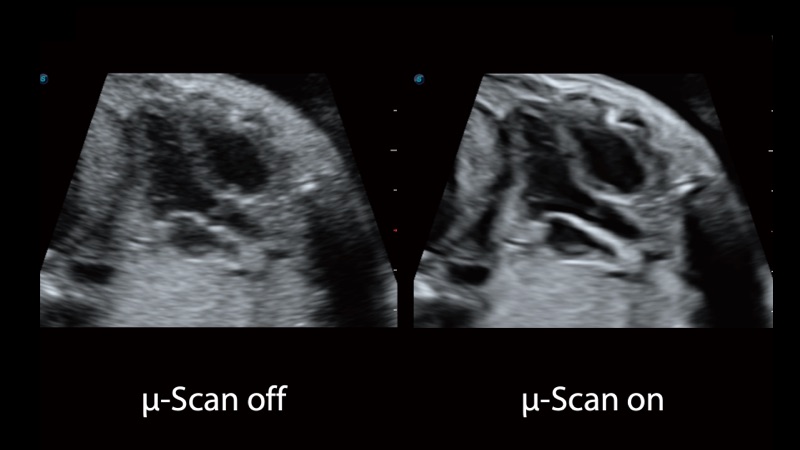

凭借狗万官方网站先进的成像技术和优异的探头技术提供的清晰的图像表现,您可以更自信地做出临床决策。